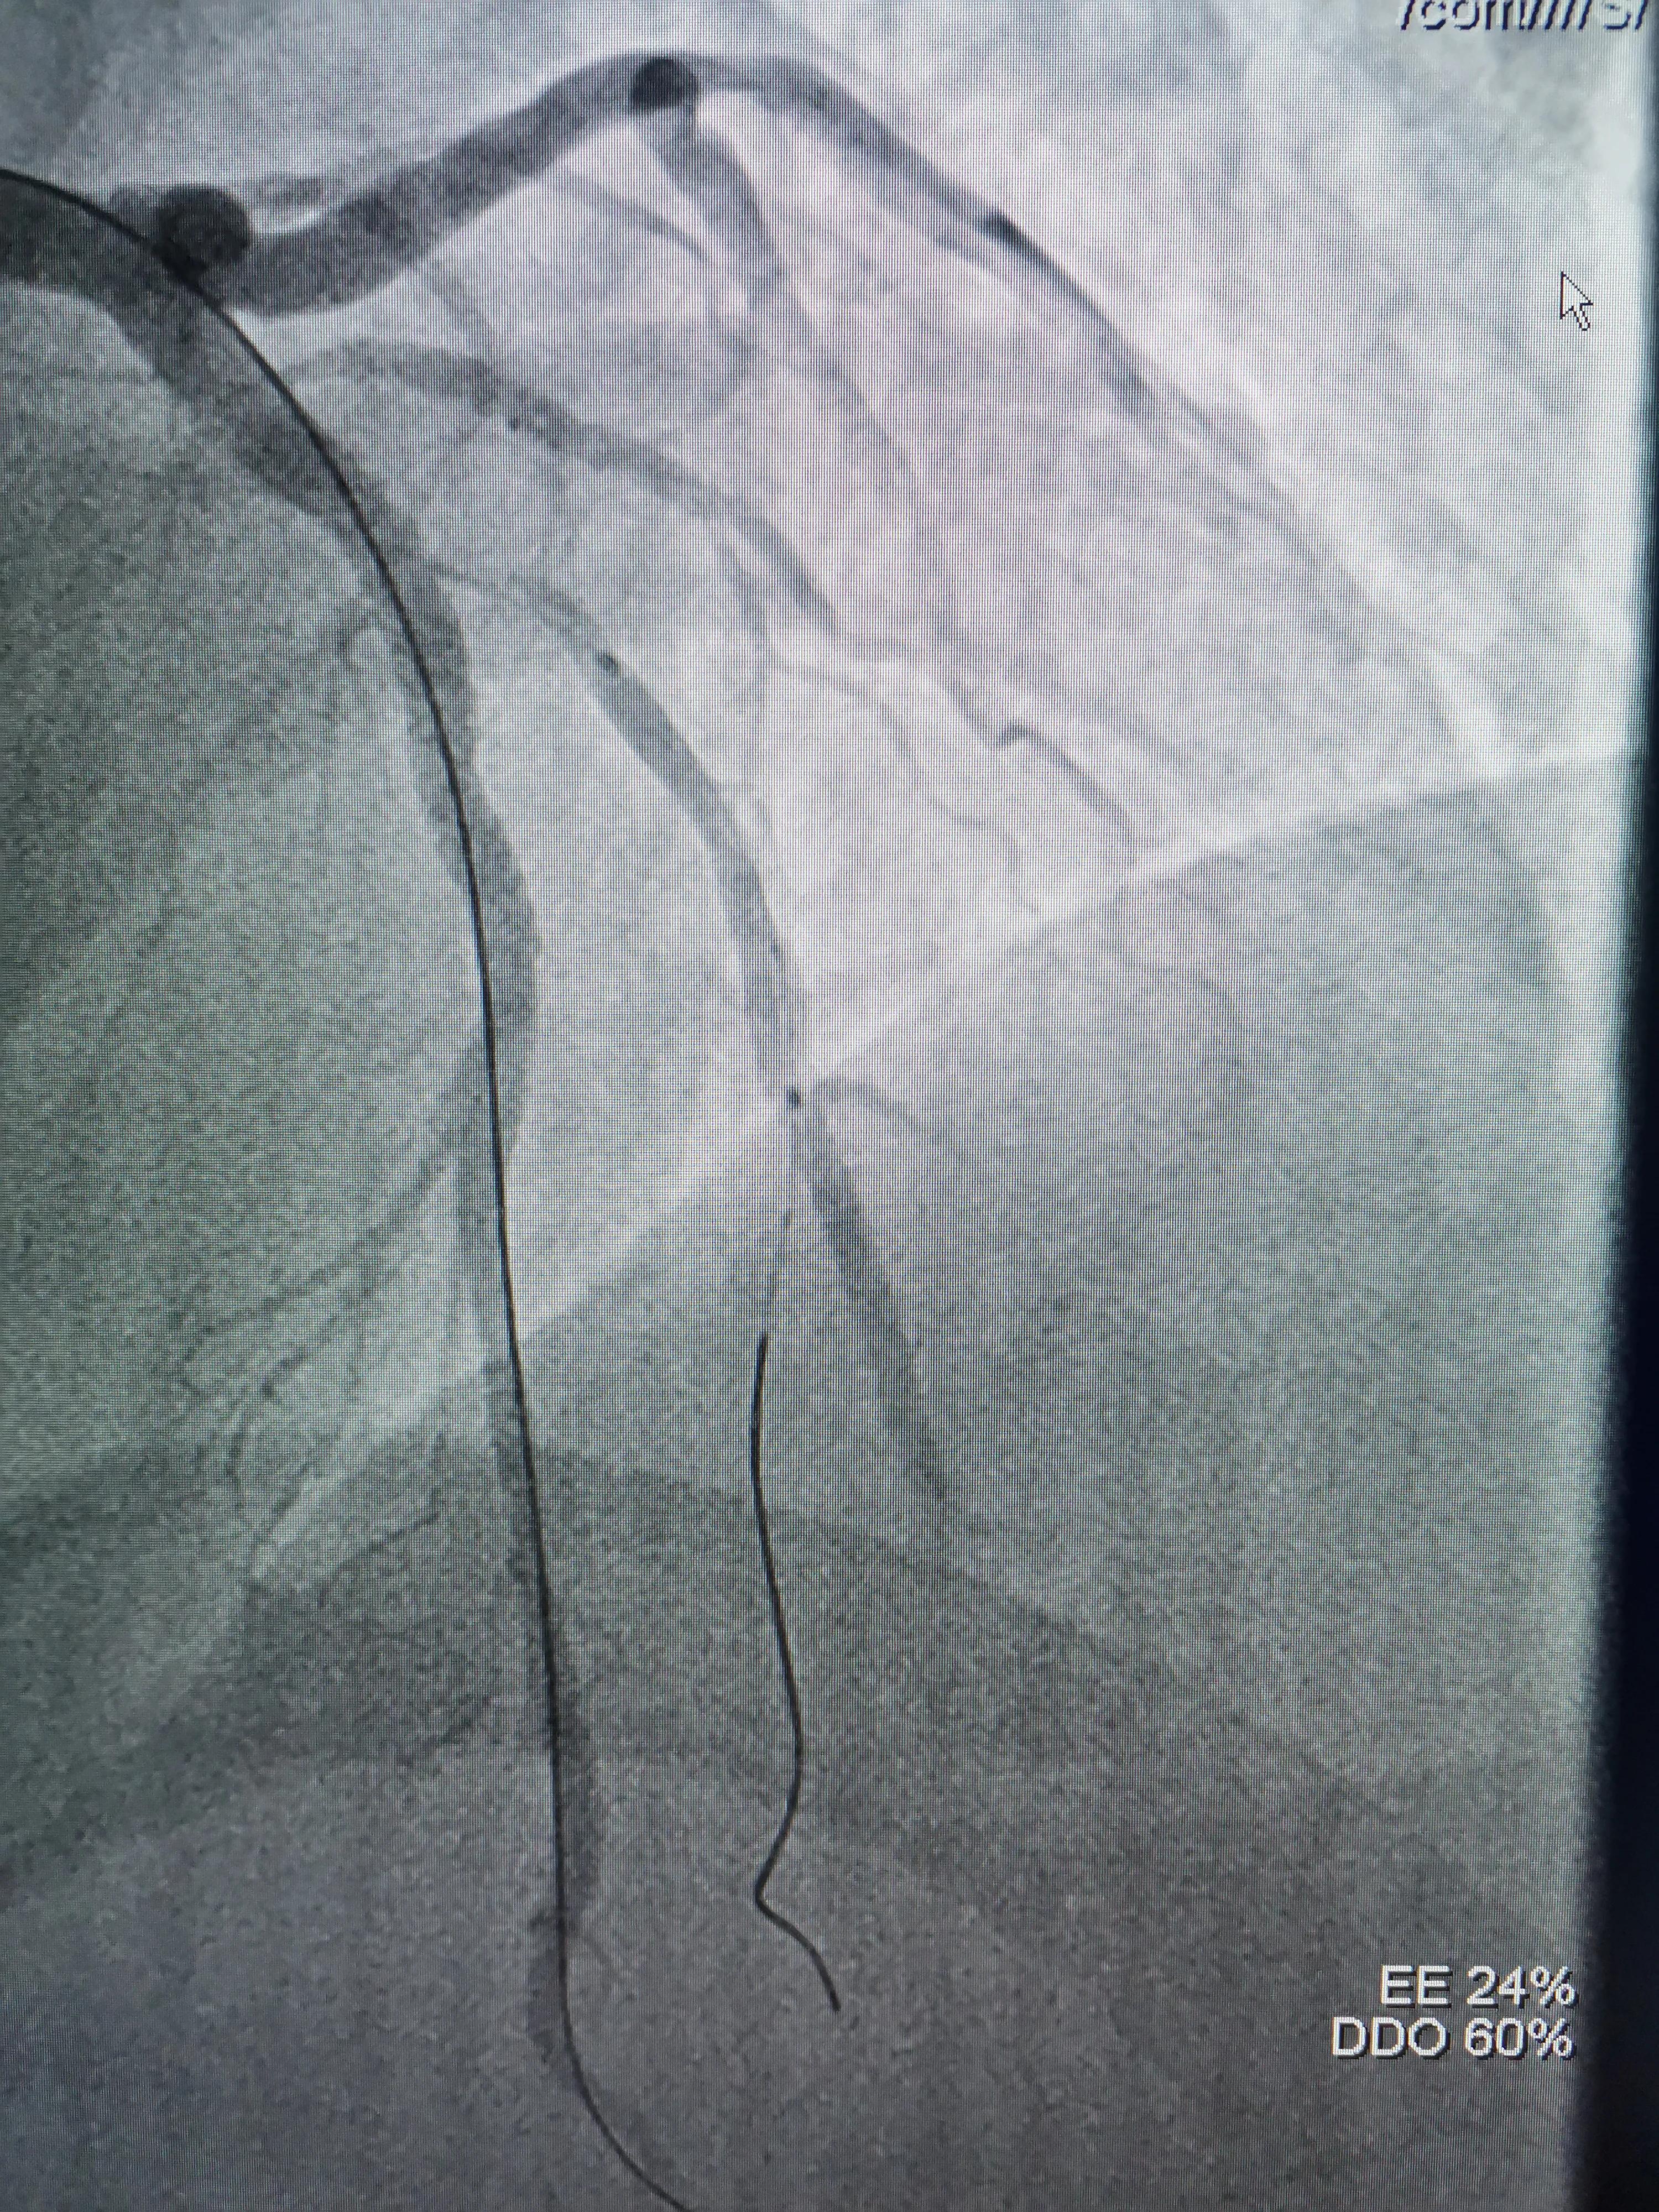

(FielderXT导丝到LAD远端)